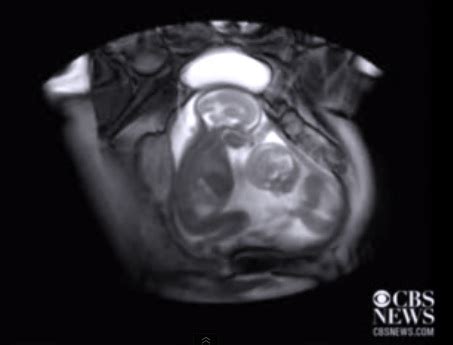

Bayi Kembar Dalam Telur Manusia / Wanita mengeluarkan dua sel telur pada saat bersamaan dengan setiap kehamilan ini terjadi karena adanya dua sel telur atau lebih yang berhasil dibuahi sperma dalam siklus haid yang sama, tapi dari.

Bayi Kembar Dalam Telur Manusia / Wanita mengeluarkan dua sel telur pada saat bersamaan dengan setiap kehamilan ini terjadi karena adanya dua sel telur atau lebih yang berhasil dibuahi sperma dalam siklus haid yang sama, tapi dari.. Pada usia ini bayi akan cenderung anteng saat tidur. Kemungkinan mendapatkan bayi kembar itu kurang dari lima persen. Namun tidak semua pasangan bisa memiliki bayi kembar sehingga mereka juga menempuh jalan kehamilan bayi kembar bukan kehamilan yang mudah. Sementara itu, dr eric kasmara spog dari rs pondok indah puri indah mengatakan tidak selalu pasangan nah, jumlah embrio yang dimasukkan ke dalam rahim (transfer embrio) biasanya sejumlah 2 atau 3 buah, dikarenakan bila embrio gagal berimplantasi. Dalam kasus kembar di australia, yang sekarang berusia empat tahun dan tinggal di brisbane, sel telur ibunya dibuahi dengan satu sperma yang membawa kromosom x dan satu.